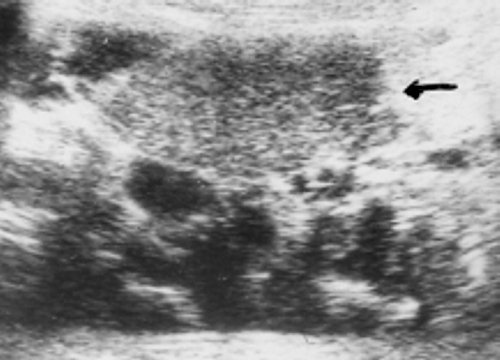

Больной, 6 лет. Родители заметили утолщение левой нижней половины шеи, при ультразвуковом исследовании диагностирована киста в области нижнего полюса левой доли. При осмотре в клинике МНРЦ в области нижнего полюса левой доли пальпируется плотное образование величиной 2х1 см. Ультразвуковое исследование: у нижнего полюса левой доли железы, смещаяя ее кверху, определяется полостное образование, в области верхней стенки прослеживается тонкая ножка кисты, идущая вдоль трахеи (рис. 4).

Рис. 4. Эхограмма в косой проекции - отчетливо определяется кистозное образование и фрагмент ножки (стрелка).